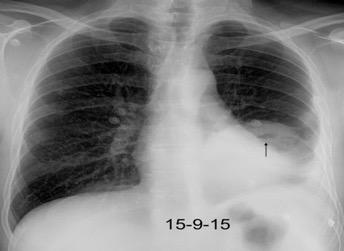

Neumonía a neumococos base izda. con derrame que aumenta.

Broncograma en lateral y en US.

(36-66% en ingresados)